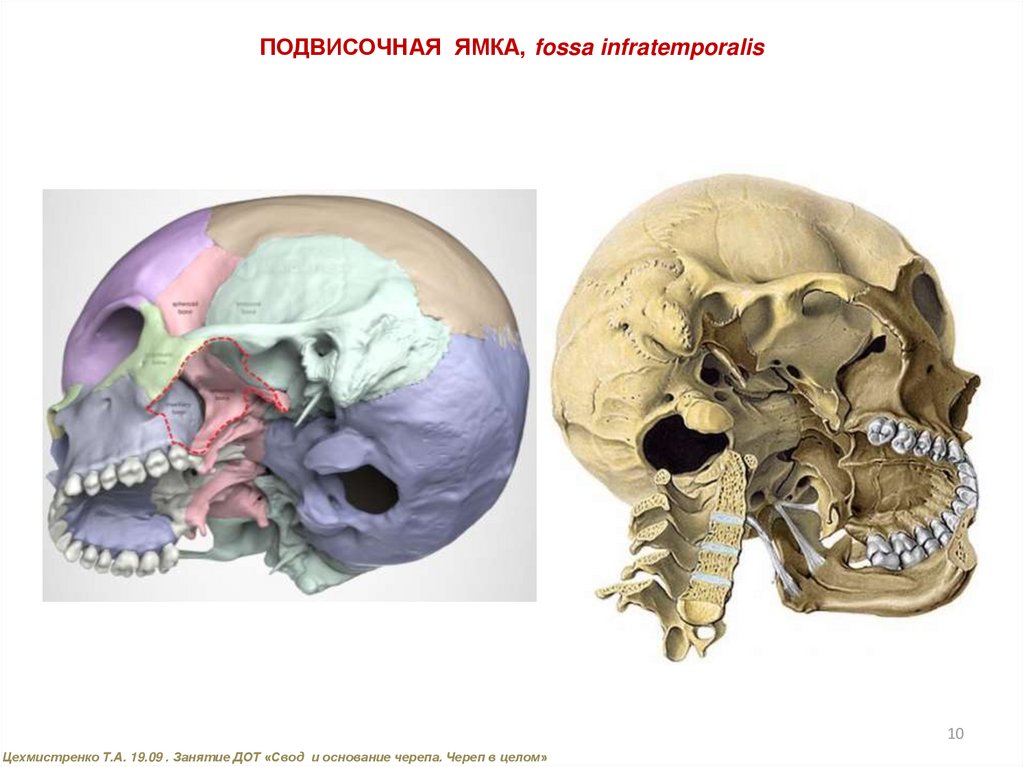

Анатомические особенности: фотографии ямок черепа, височной и подвисочной крылонебной